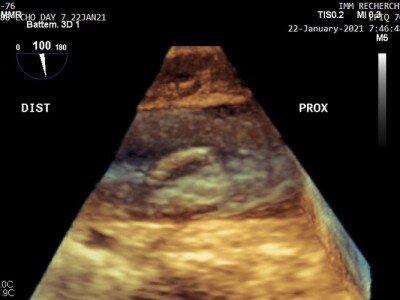

Учёные разработали удобное новшество в медицинской отрасли — ультразвуковой пластырь, способный сканировать динамику сердечной мышцы в режиме реального времени. Он также использует глубокое обучение для автоматического расчёта объёма желудочков и создания статистики производительности человеческого «мотора». В устройстве присутствуют пьезоэлектрические датчики для визуализации глубоких тканей. Между тем растягивающиеся электроды из жидкого металла обеспечивают не только необходимую близость ультразвукового сканера к коже, но и возможность создания сложной и компактной конструкции, что раньше было недостижимо. Однако устройство всё ещё нуждается в подключении к внешней системе обработки данных через кабель. Команда работает над миниатюризацией и надеется улучшить разрешение изображения за счёт более совершенных алгоритмов. Также планируется использовать ещё больший набор данных для обучения ИИ. Носимый ультразвуковой датчик сможет обеспечить непрерывную метрику для пациентов с сердечным

Учёные разработали удобное новшество в медицинской отрасли — ультразвуковой пластырь, способный сканировать динамику сердечной мышцы в режиме реального времени. Он также использует глубокое обучение для автоматического расчёта объёма желудочков и создания статистики производительности человеческого «мотора».

В устройстве присутствуют пьезоэлектрические датчики для визуализации глубоких тканей. Между тем растягивающиеся электроды из жидкого металла обеспечивают не только необходимую близость ультразвукового сканера к коже, но и возможность создания сложной и компактной конструкции, что раньше было недостижимо.